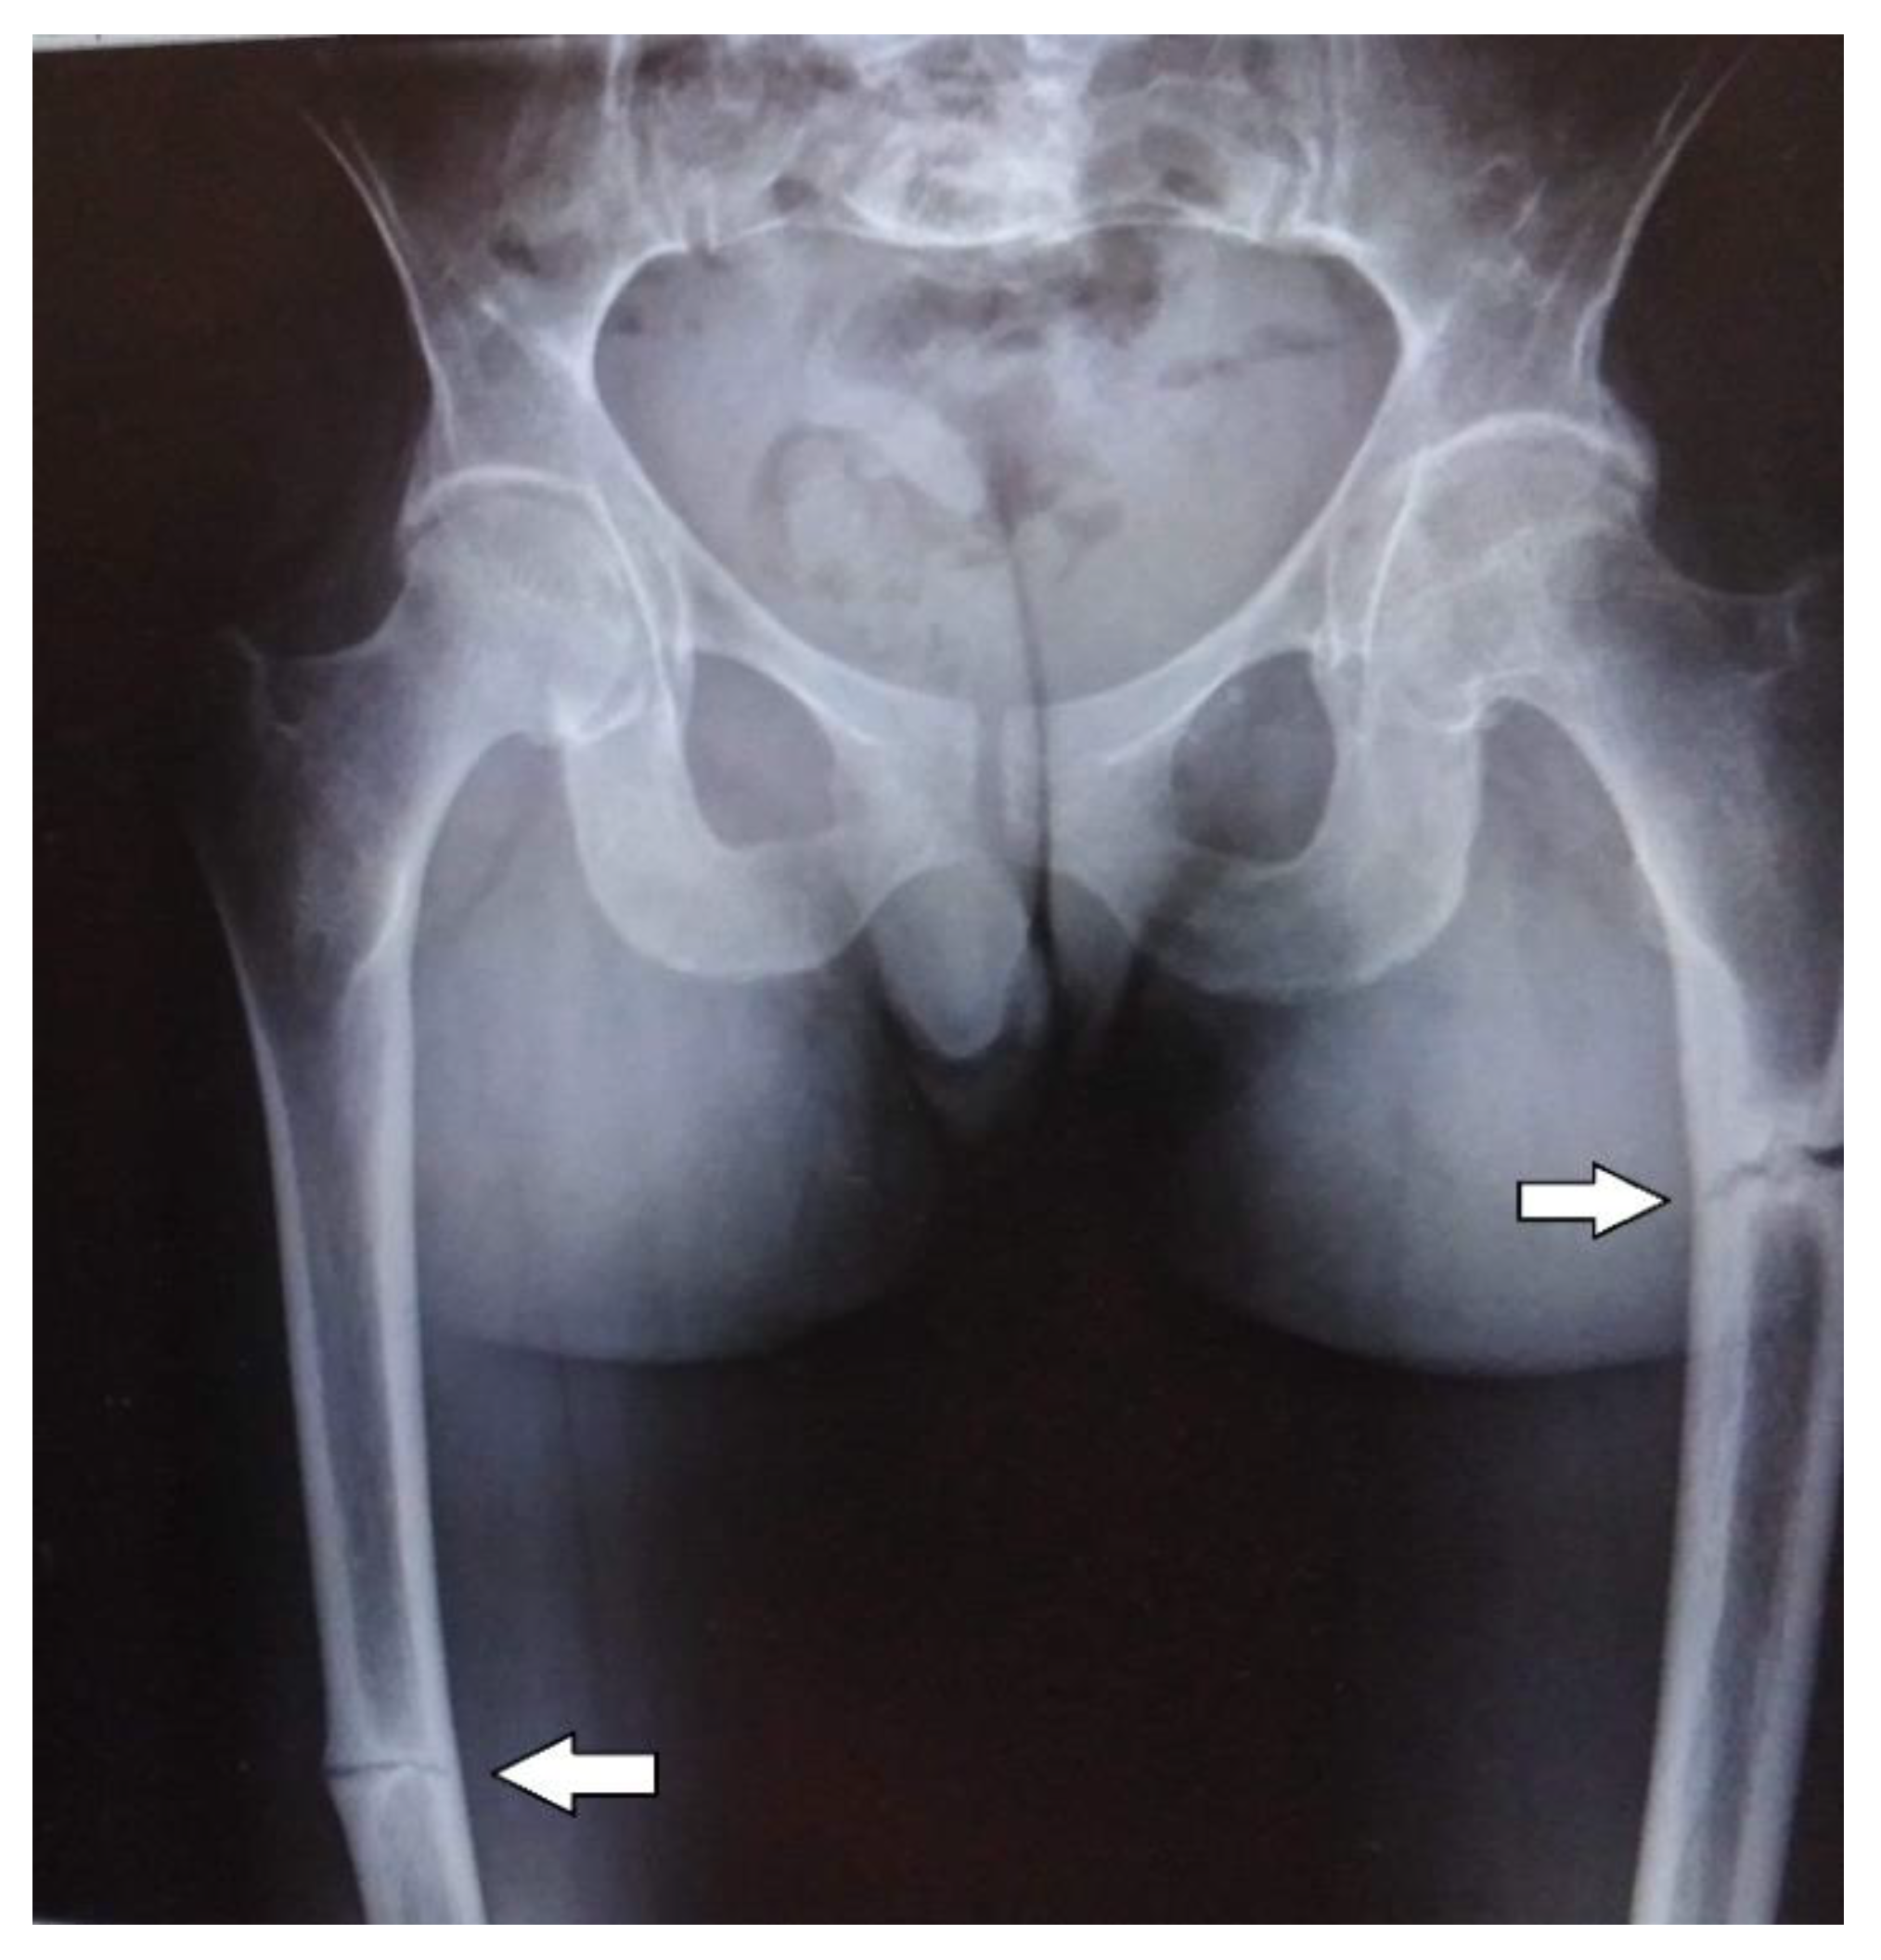

The abdominal ultrasound examinations showed the features of urolithiasis in 3/16 patients, and the X-ray examinations revealed the most common disorders of bone mineralization, abnormalities in the epiphysis of long bones–dilatation, uneven contours, bone defects, and fractures (Figure 1 and Figure 2).

Bone structure abnormalities observed in X-ray were characteristic and most severe for the perinatal and infantile types (they occurred in all the patients of these groups), while in other HPP types, they occurred much less frequently. A decrease in bone mineral density, assessed by densitometry, was observed in the infantile and childhood types, but it should be noted that bone demineralization was described in the perinatal type on bone radiography. In this case, DXA was not performed due to the severe patient’s condition.

Figure 2. Fractures of the femurs in an adult patient with infantile HPP.